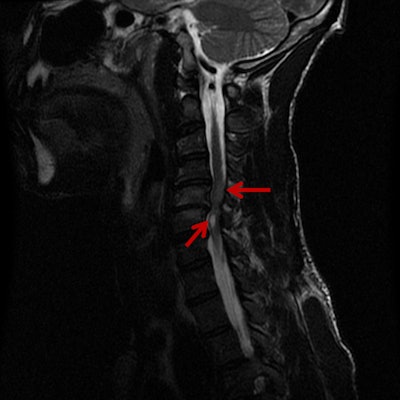

Chundru and colleagues decided to dig deeper into the phenomenon by analyzing data collected from 2014 to 2016 by the trauma surgery department. This included the mechanism and severity of injury, whether the patient was wearing a helmet, blood alcohol content, and toxicity screening results.

They found that both the number and severity of injuries were indeed rising, and the difference was statistically significant. The total number of bicycle injuries rose from 138 cases in 2014 to 169 cases in 2016 -- an increase of 22.5%. The injury severity score (ISS) also rose over the study period, from an average ISS of 4.03 in 2014 to 4.47 in 2016.